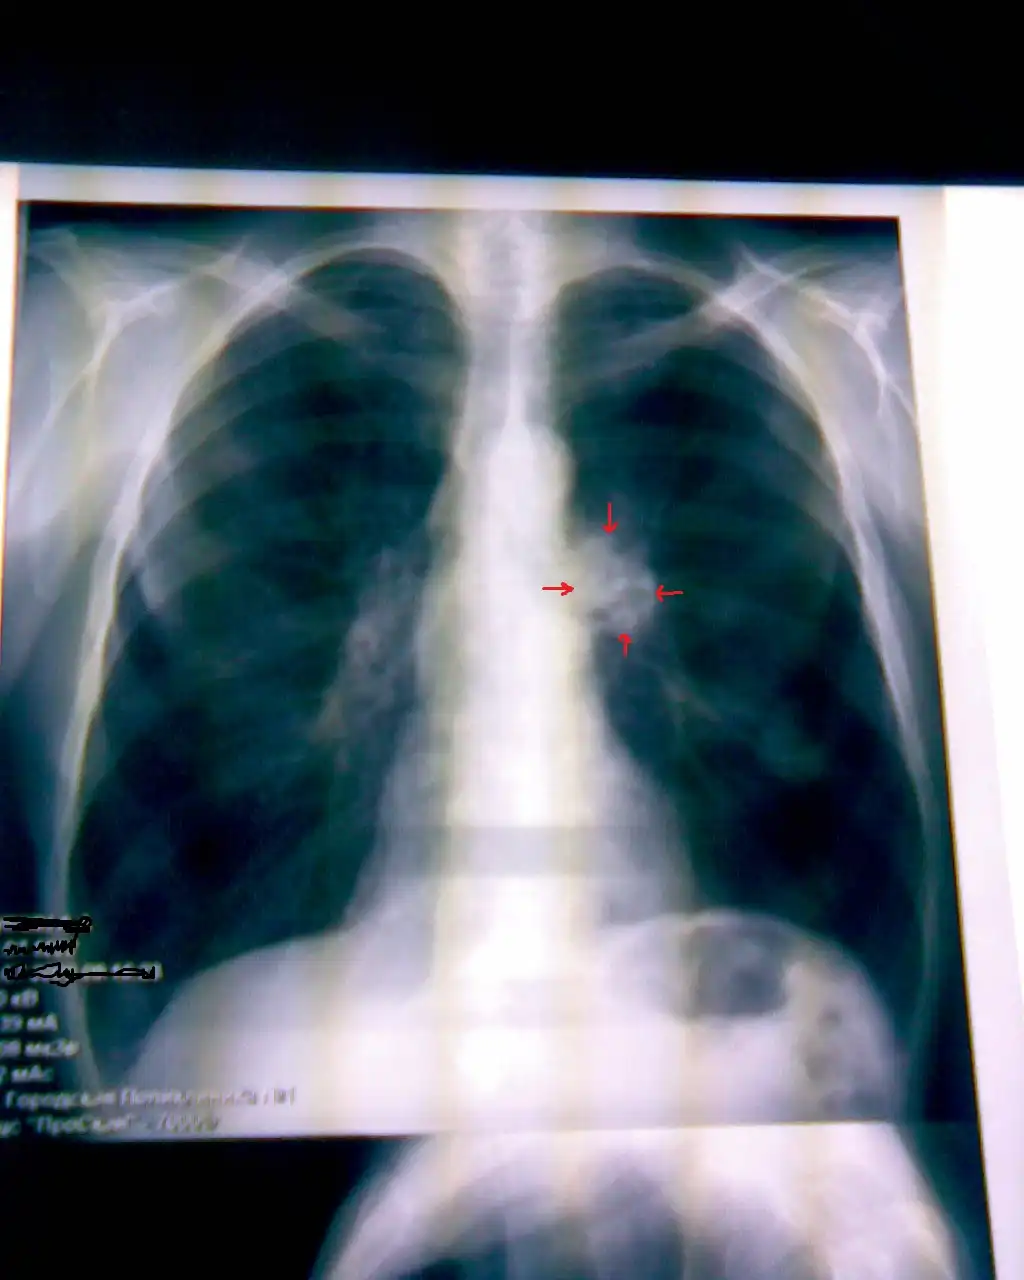

Пациент №2:

Флюорограмма: